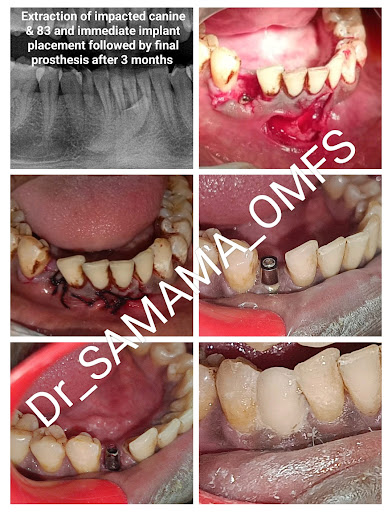

Gallery